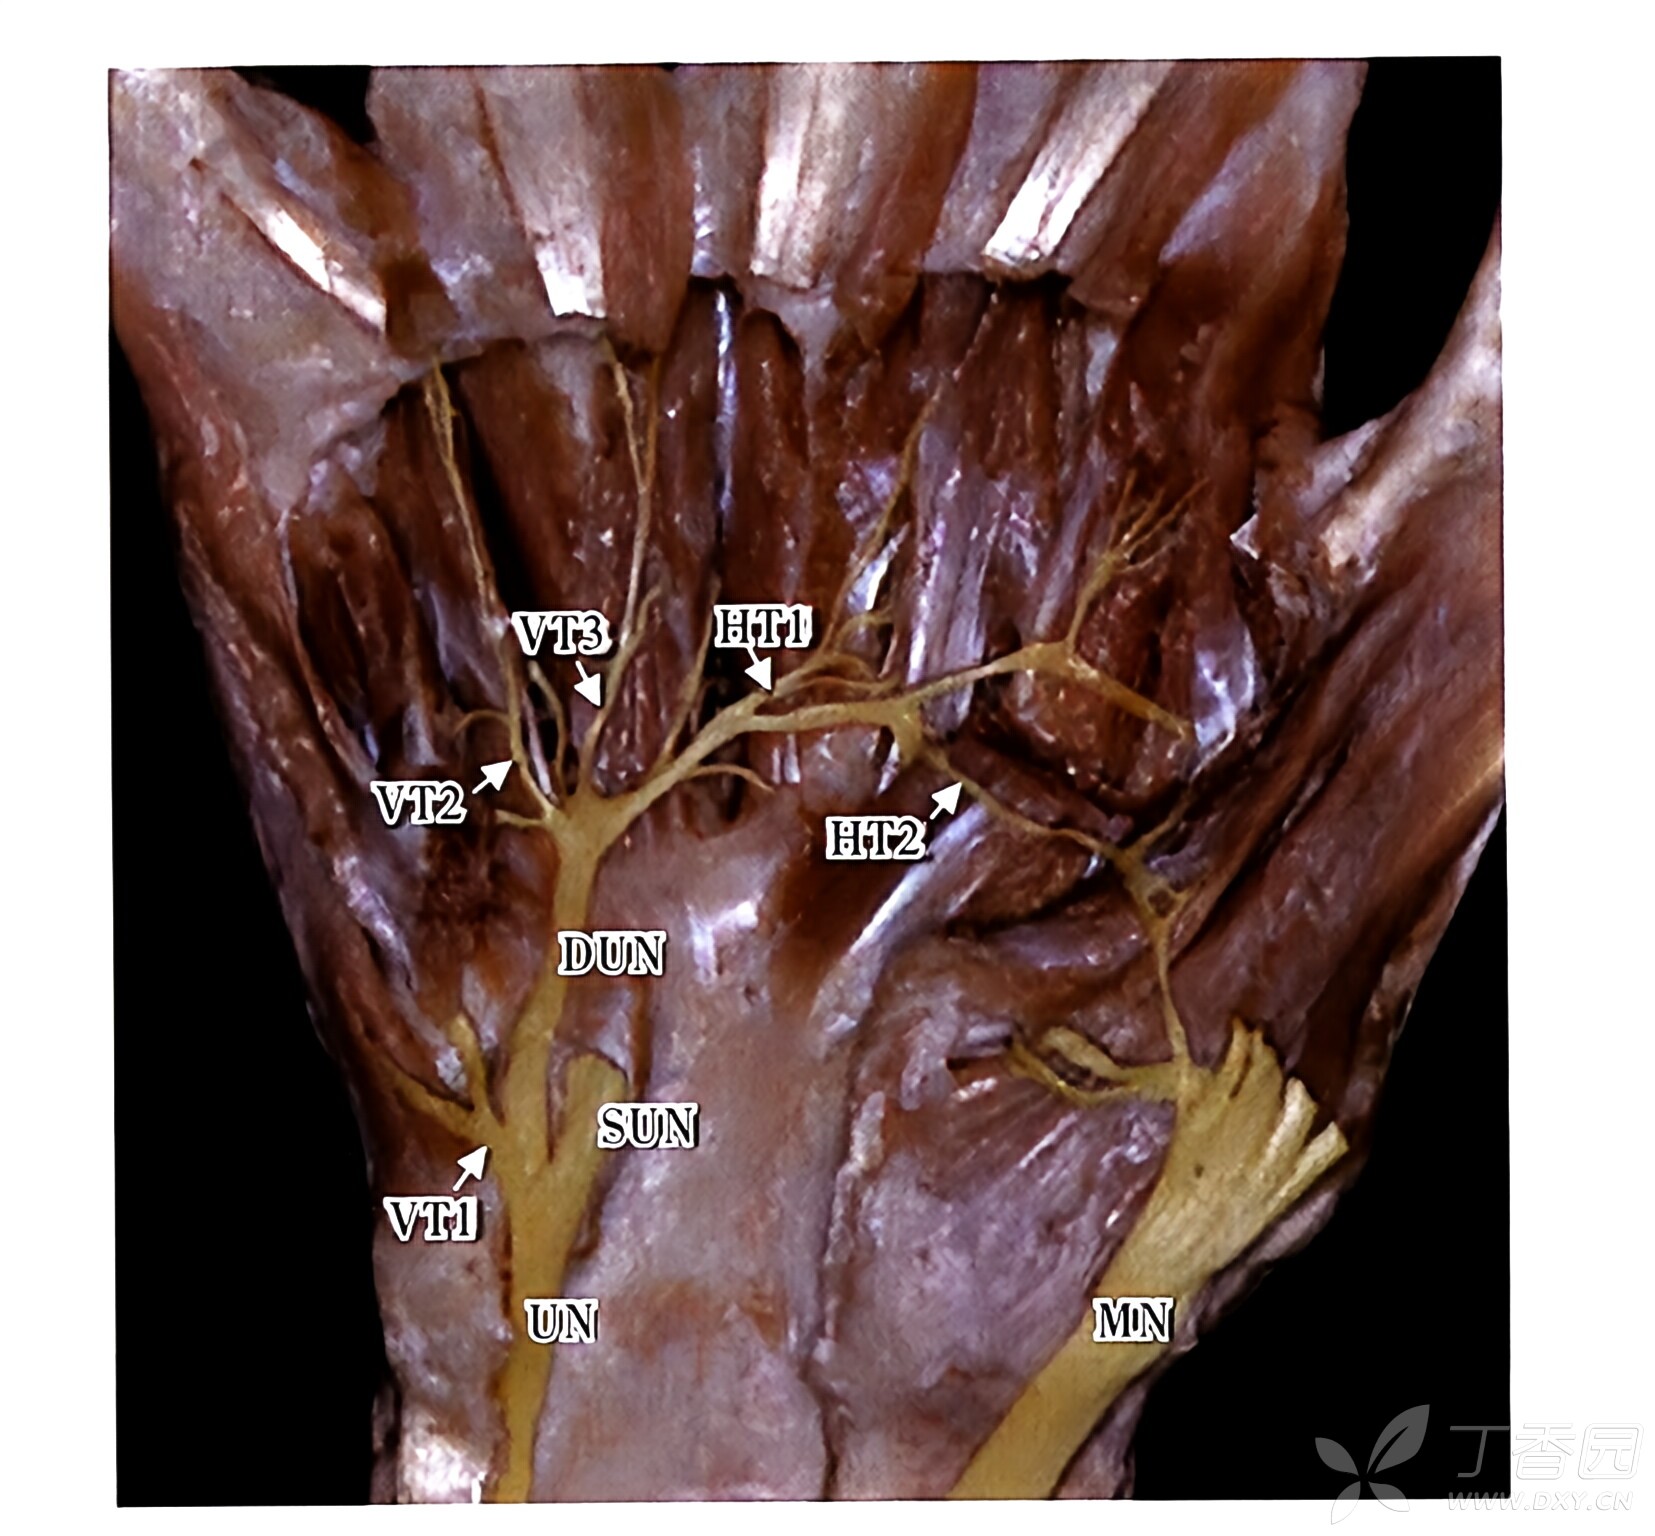

图 5

尺神经掌深支

7

注:VTs(vertical trunks)为垂直支;VT1为第一垂直支;VT2为第二垂直支;HTs(horizontal trunks)为横支;HT1为第一横支;HT2为第二横支;DUN(deep branch ofulnar nerve)为尺神经深支;SUN(superficial branch ofulnar nelve)为尺神经浅支;UN(ulnarnerve)为尺神经;MN(median nerve)为正中神经。尺神经出豆钩管、绕钩骨钩转而外行,经掌深弓走行于骨间肌前方,依次发出小指展肌支、小指短屈肌支、小指时掌肌支和第4、3、2、1骨间肌支,以及第4、3蚓状肌支、拇收肌斜头支、拇收肌横头支等